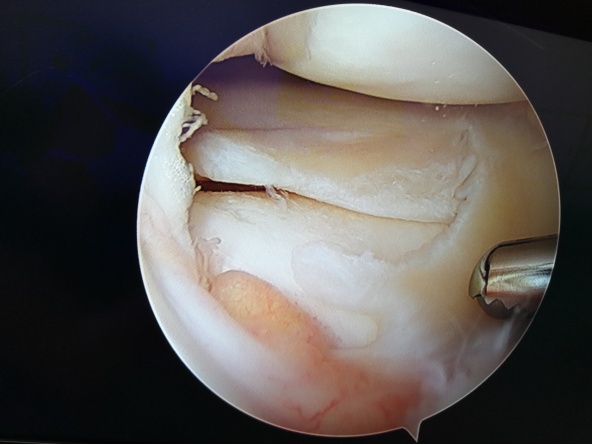

① 关节镜:是使用特殊设备通过小切口进行的微创手术。医生使用关节镜观察关节间隙。可以清除受损的软骨或松散的颗粒,清洁骨骼表面,处理破损的半月板,并在发现这些损坏的情况下修复其他类型的组织。该手术常用于年轻患者(55岁及以下),以延迟更严重的手术。

② 关节软骨修复术:关节软骨修复术包括自体骨软骨移植、软骨细胞移植和微骨折等技术,对年轻、单处小面积负重区软骨缺损、活动量大的患者疗效显著,对老年患者、激素引起坏死、多处损伤等患者疗效较差。